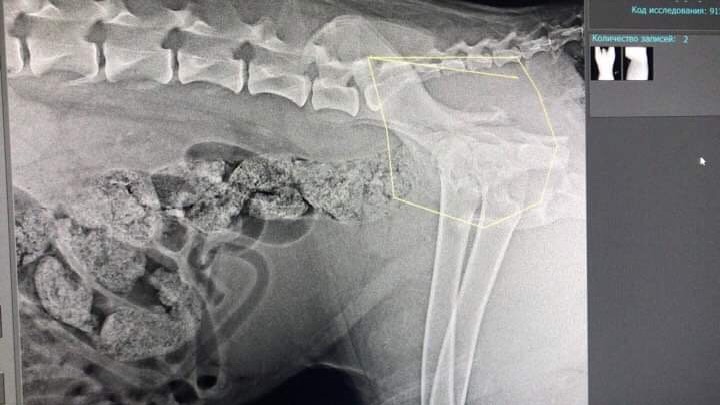

Двойной перелом таза без смещения. Чипа нет. Клеймо не рассмотреть -очень волосатое брюхо.

"надо показать снимки собаки специалистам,перелом со смещение,может надо оперировать и ставить пластину"

У собаки еще и пироплазмоз обнаружили

Обязательно надо но только после восстановления от пирика. А за эио время уже может успеть непоавильно сростисьДайвер писал(а):Мила, а что с тазом, оперировать не надо?